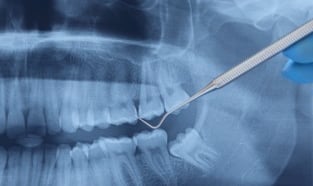

Affordable Dental X-Ray Dentist Office in New York City

DENTAL X-RAYS